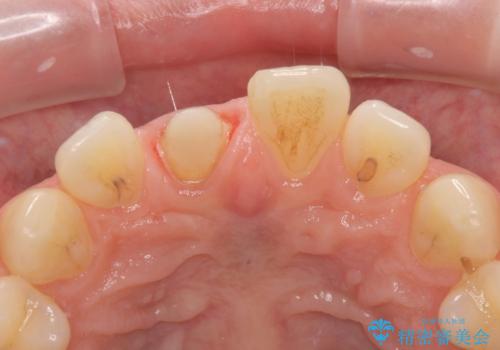

- 数年前に前歯のセラミック治療を行い、そのやり替えを希望して来院された患者様です。

先端が欠けてしまっていて、色も少し不自然な印象があります。

空隙がある歯並び改善のため、矯正治療も提案しましたが希望せれず、隣の歯も一緒に被せものにして、

大きさをそろえることも希望されなかったため、一本だけやり替えていくととしました。